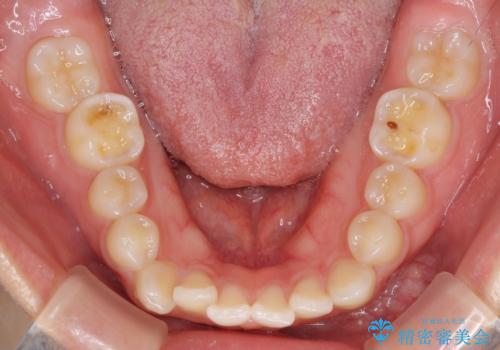

- ハーフリンガル

- 前歯のデコボコや八重歯、舌癖による開咬を気にして来院された患者様です。

目立たない装置を希望されたので、上顎が裏側装置のハーフリンガルを選択し、上顎小臼歯1本を抜歯して、補助装置を併用して矯正治療を行うこととしました。

補助装置を事前に使用したことで、あっという間に八重歯が改善し、ハーフリンガルにしては1年半もかからずに治療を終えることができました。